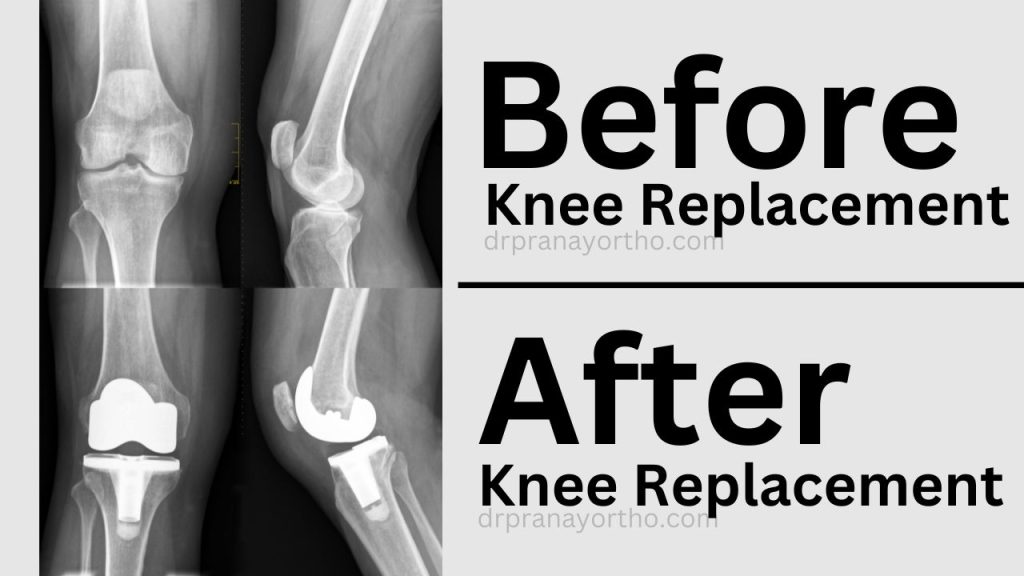

Knee replacement surgery involves removing damaged cartilage and bone from the knee joint and replacing it with artificial components known as implants. This surgical option is often recommended for individuals who have not found relief through non-surgical treatments such as medication, physical therapy, or lifestyle changes.

- Perform physical examinations and diagnostic imaging (X-rays, MRIs) as needed.